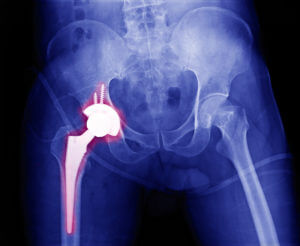

Hip replacement surgery is also called total hip arthroplasty. It is a surgical method for fixing damaged hip joints.

During the surgery, the doctor removes the parts of the hip that are damaged by arthritis. These are replaced with metal, ceramic, or plastic parts.

This new joint helps reduce pain and makes it easier to move.